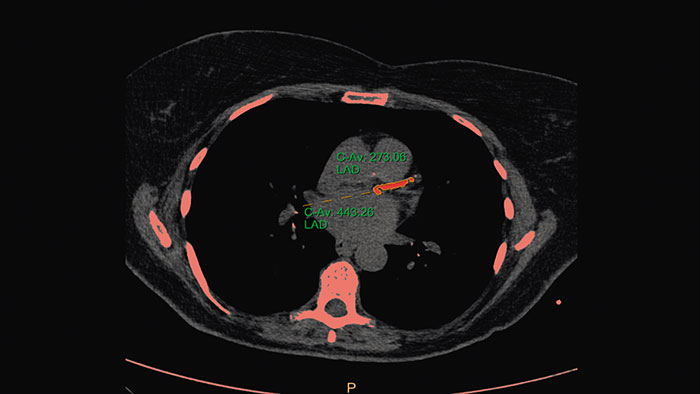

- Calcium Scoring

-

CT Calcium Scoring

One-click 3D calcium segmentation

One-click 3D segmentation and quantification for coronary arteries calcifications including mass, Agatston, and volume scores.

Benefits

- Calcium scoring is achieved by performing automatic calculations on CT HU values in user-defined regions of interest.

- Supports ECG-gated and non ECG-gated images in DICOM format from Philips and other vendors (mass score can only be calculated for Philips CT scanners).

- The application incorporates parameters from the MESA (Multi Ethnic Study of Atherosclerosis) database.